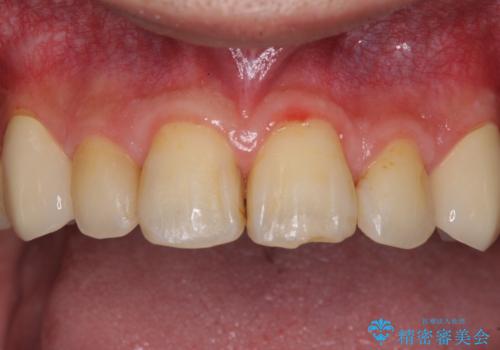

- 以前矯正を行った際に前歯が虫歯だらけとなり、審美面を気にして来院された患者様です。

虫歯の大きかった左右犬歯はオールセラミッククラウンで補綴治療をおこない、4前歯は研磨や古い充填物の詰め直しを行いました。

歯並びは良くなったものの、着色が気になって口元を見せることを躊躇していた用ですが、治療後は他人の視線を気にすることがなくなったようで、大変満足していただきました。